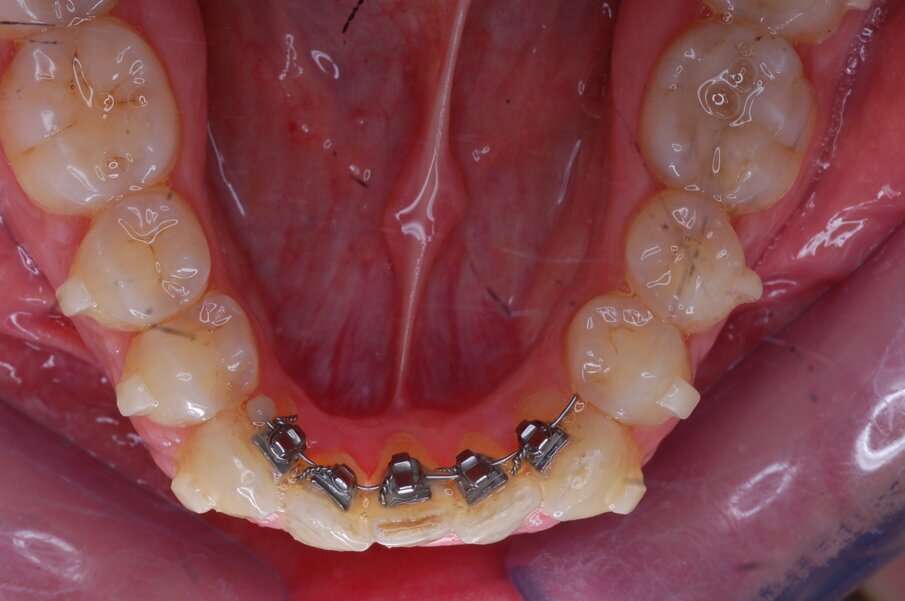

Diagnosi ed eziologia Un uomo sano di 39 anni si è presentato nel nostro studio ortodontico lamentando un aspetto dentale poco attraente e la paura della chirurgia ortognatica proposta da un altro ortodontista. Clinicamente, il profilo del paziente era rettilineo e la vista frontale non mostrava alcuna asimmetria facciale. L’esame funzionale non ha rivelato alcuna deviazione mandibolare o riduzione dei movimenti. Il paziente non aveva dolori articolari e non sono stati rilevati rumori articolari. Era presente una lieve occlusione molare bilaterale di Classe II, un morso aperto e un grave affollamento in entrambe le arcate. L’affollamento era particolarmente grave nell’arcata mandibolare, sebbene mancasse l’incisivo centrale mandibolare destro. Gli incisivi mascellari erano di piccole dimensioni, suggerendo una discrepanza dell’indice di Bolton se fossero stati presenti tutti e quattro gli incisivi mandibolari. Erano inoltre presenti un morso incrociato nella regione dell’incisivo laterale superiore sinistro e una grave rotazione distale del secondo premolare mandibolare sinistro (Figg. 1-8).

Figg. 1-8_Fotografie facciali e intraorali pre-trattamento.